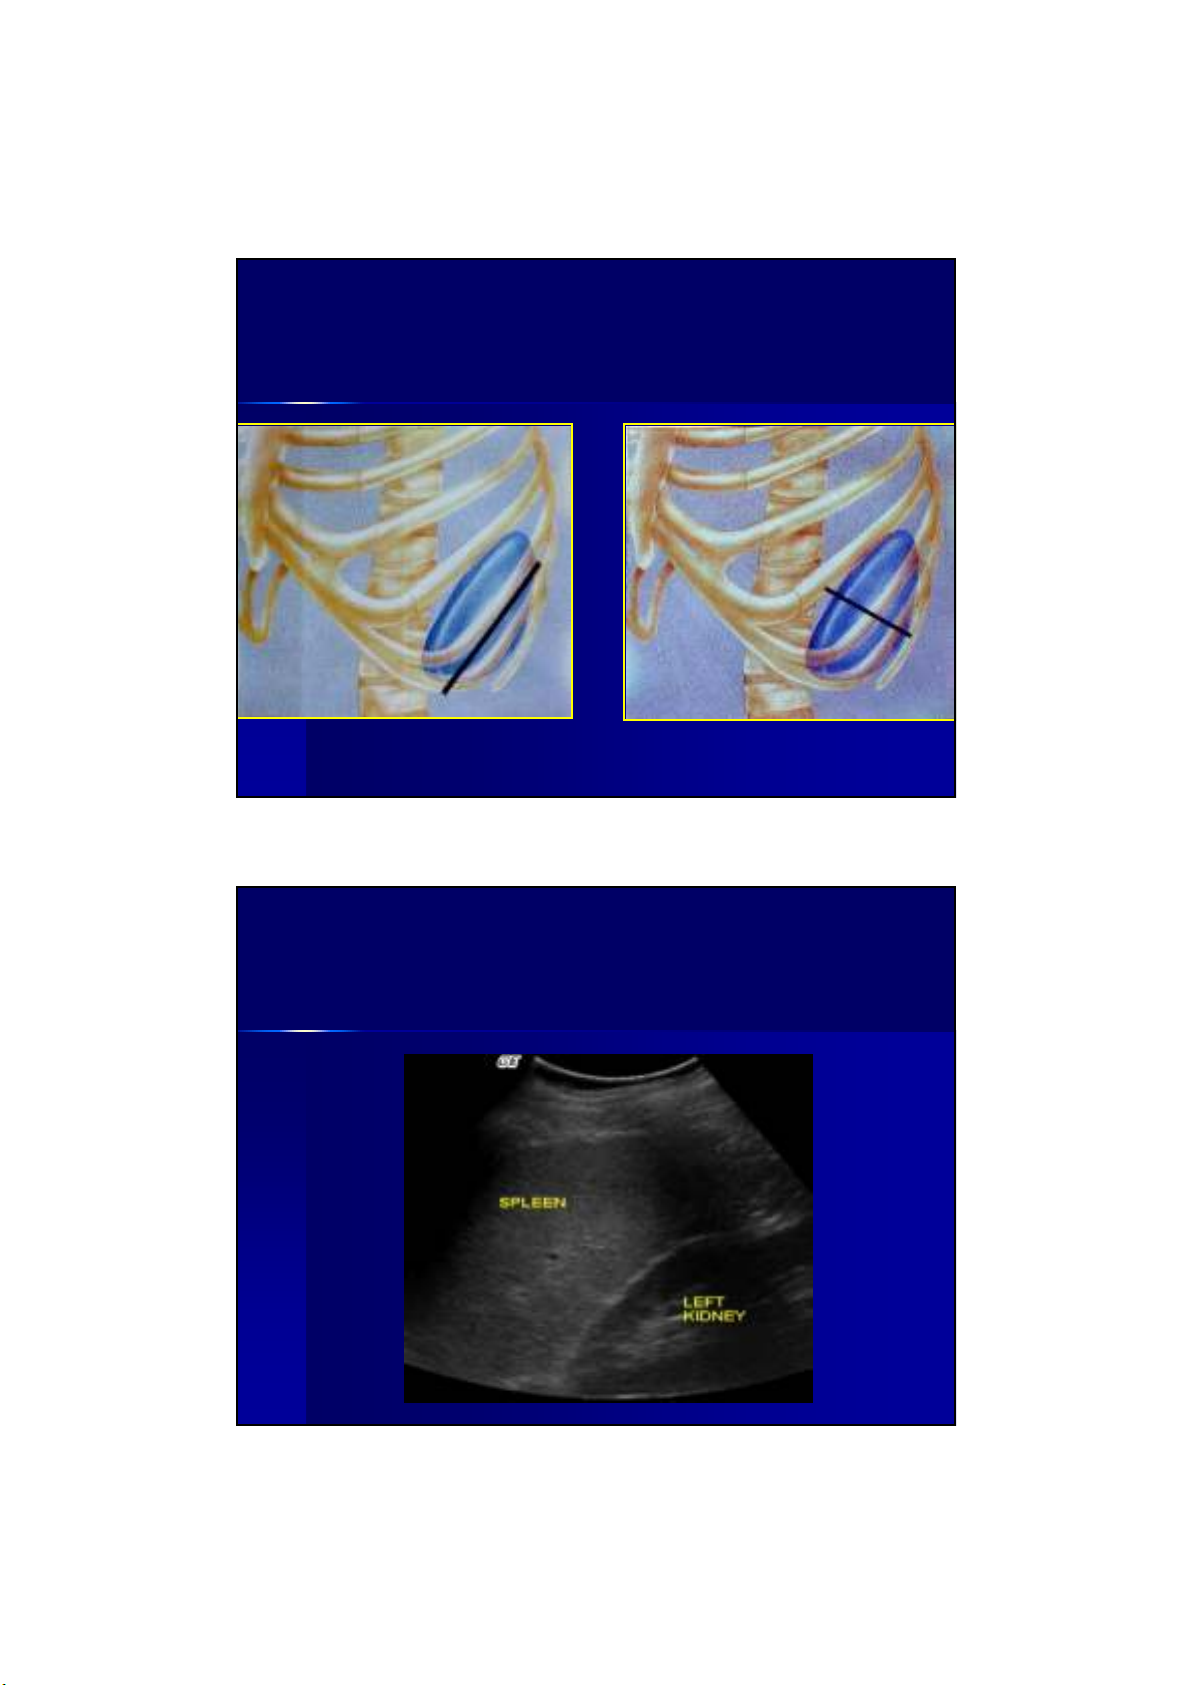

LLÁÁCH BÌNH THCH BÌNH THNGNG